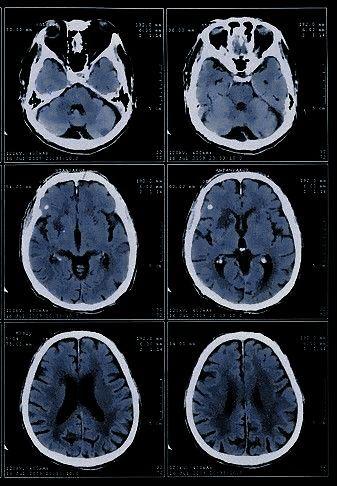

Şizoaffektif bozukluğun kesin nedenleri tam olarak bilinmemektedir ancak genetik yatkınlık, beyindeki nörotransmitter dengesizlikleri ve çevresel etmenlerin (travma, stres) etkili olduğu düşünülmektedir. Aile öyküsü olan bireylerde bozukluğun gelişme riski daha yüksektir (Hirschfeld & Klapper, 2006).